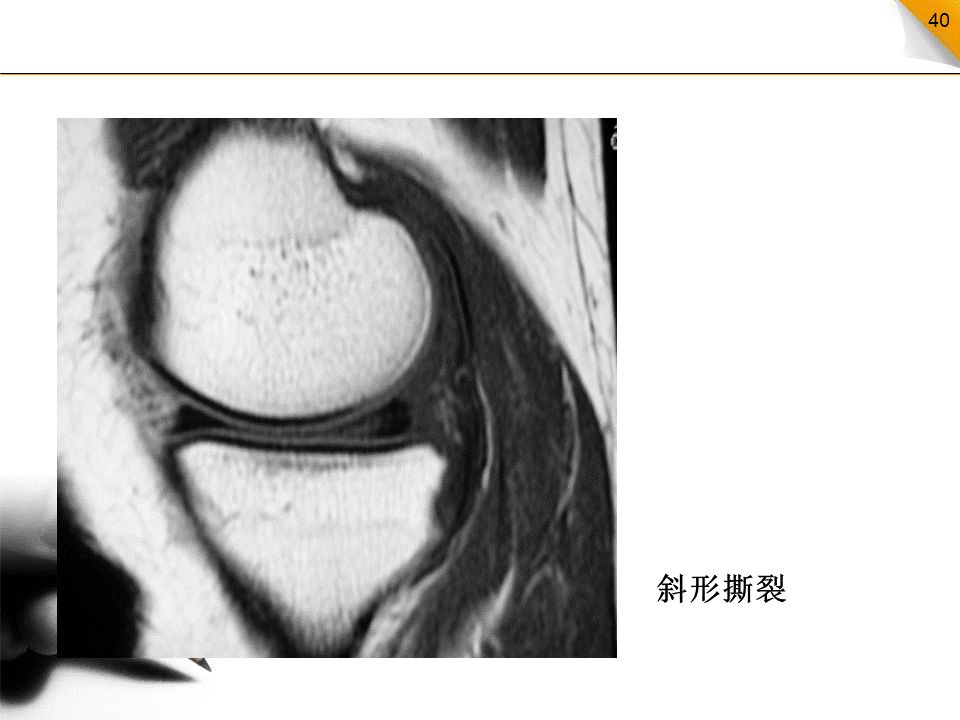

半月板撕裂的分类

水平撕裂:比较少见,高信号的方向与胫骨平台平行,内缘达半月板的游离缘垂直撕裂:其高信号的方向与胫骨平台垂直斜行撕裂:最常见类型,高信号的方向与胫骨平台成一定的角度纵行撕裂:高信号的方向与半月板的长轴方向平行放射状撕裂:高信号的方向与半月板的长轴方向垂直,好发于外侧半月板的内1/3部

正确分类对半月板手术方案的制定很重要